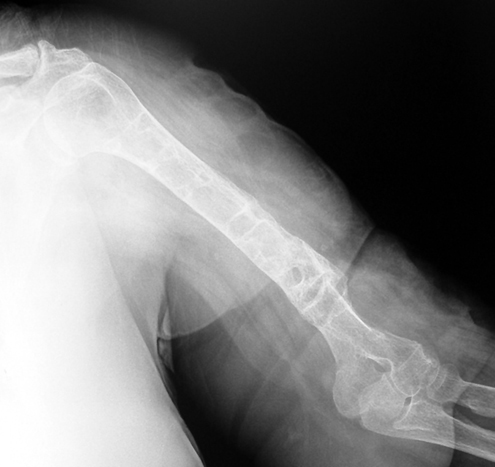

Vaka 1